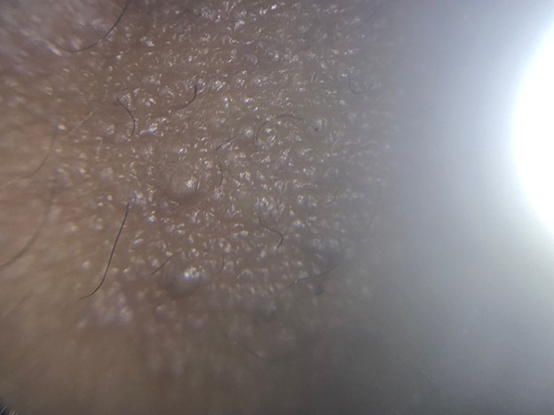

Acquired hypermelanosis of the skin is a common condition that can develop secondary to various causes, such as topical application of irritants, repeated friction, ultraviolet radiation, and aging. The submental area is generally spared from environmental insults, such as exposure to ultraviolet radiation, due to its anatomical location. However, hypermelanosis of the submental area is a common complaint that brings patients to a dermatologist. In recent times, the number of patients presenting with this problem has increased probably due to the practice of wearing masks during the COVID-19 pandemic. Usually, the typical patient is a young woman who is cosmetically conscious and is distressed with this peculiar lesion under the chin. The lesion is generally asymptomatic except for the distress that it causes the patient. However, in some cases, the patient may complain of itching or thickened or rough skin. Inspection reveals a triangular area of hypermelanosis confined to the approximately lateral half of the submental area. Sometimes the area may present discrete horny follicular prominences. Additionally, the skin may demonstrate lichenification or plaque-like thickening without any particularly distinct patterns (Figure 1). Dermoscopy of the affected area reveals well-defined follicular prominences over a background of mildly hyperpigmented skin. Some areas may demonstrate fine scales as well (Figure 2). However, signs of inflammation are absent in these lesions. The lack of symptoms and the benign dermoscopic findings suggest that a biopsy is not required in such cases.

Figure 2 Dermoscopy shows papules over a blanket of hyperpigmentation, slightly increased skin markings and fine scaling in some parts of affected area.